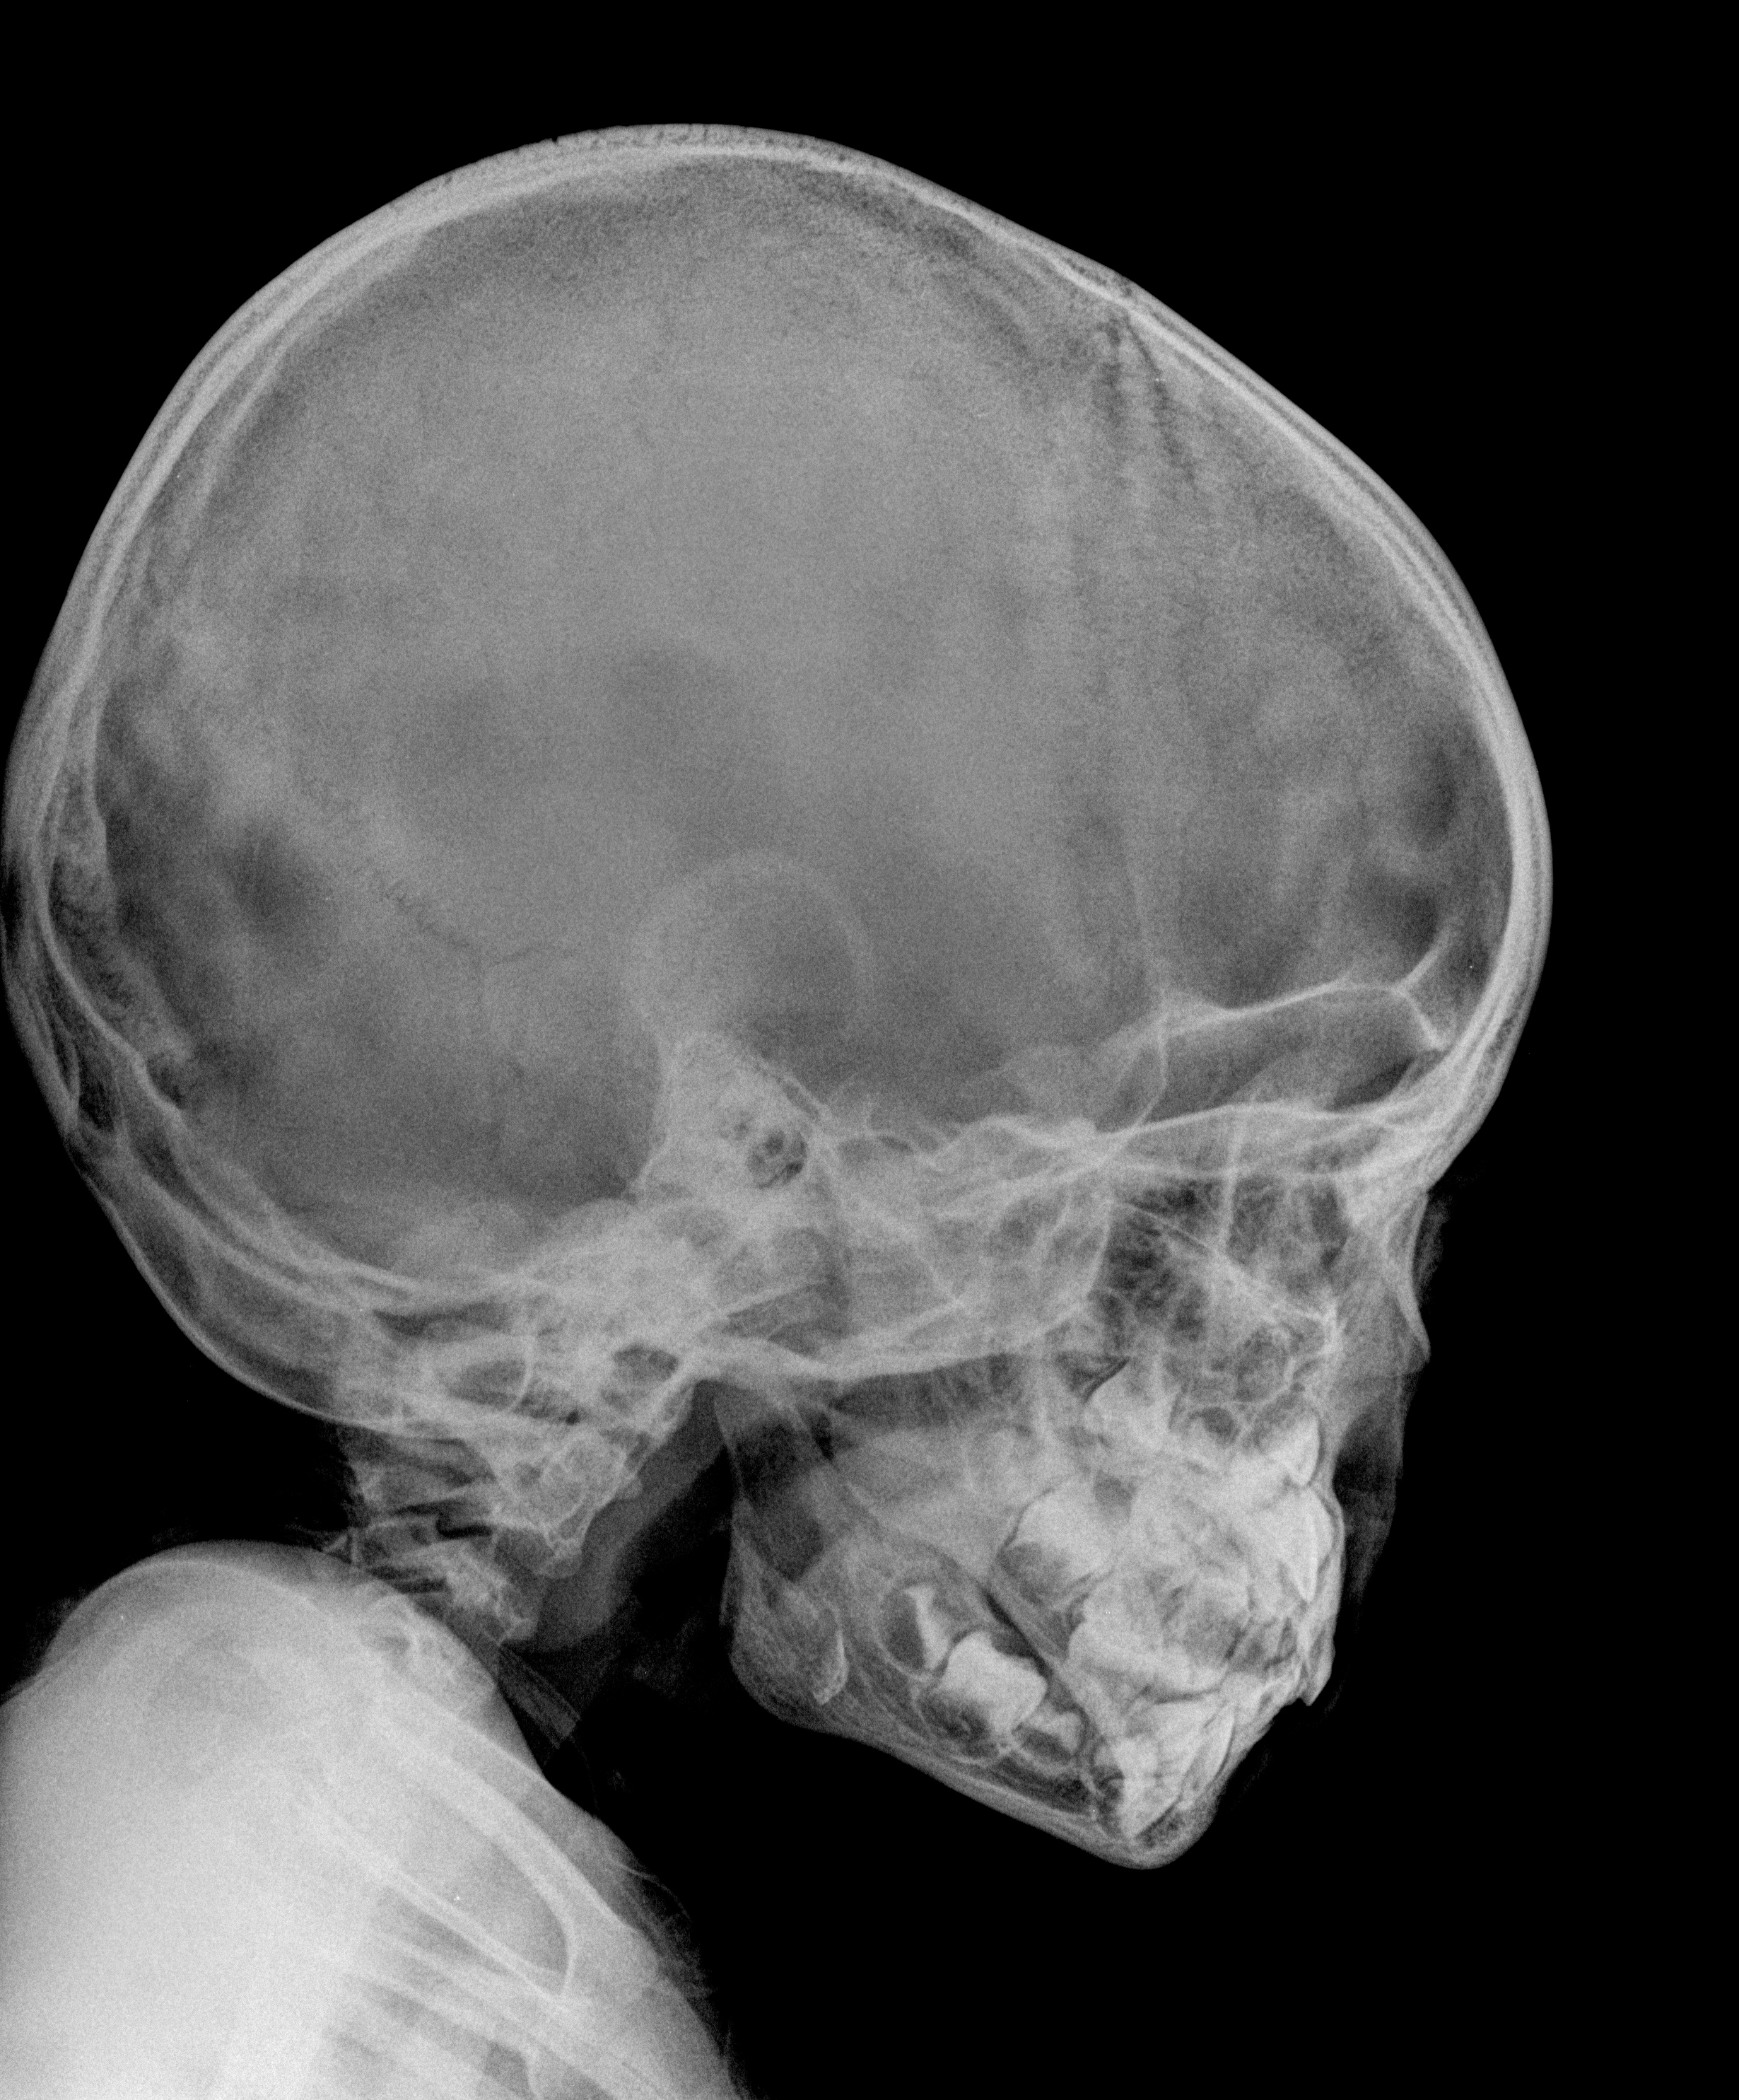

New research may help doctors treat craniofacial abnormalities while the patient is still growing—rather than having to wait until adulthood.

This is part of why children with bone deformities are often forced to wait until adulthood—until their bones stop growing—before their condition can be corrected.

“Up until now, the cells that drive this bone growth have not been understood very well. As an orthodontist myself, I have special interest in this aspect, especially for finding a cure for severe bone deformities in the faces of children. If we can find a way to make bones that continue to grow alongside the child, maybe we should be able to put these pieces of growing bones back into children and make their faces look much better than they do.”